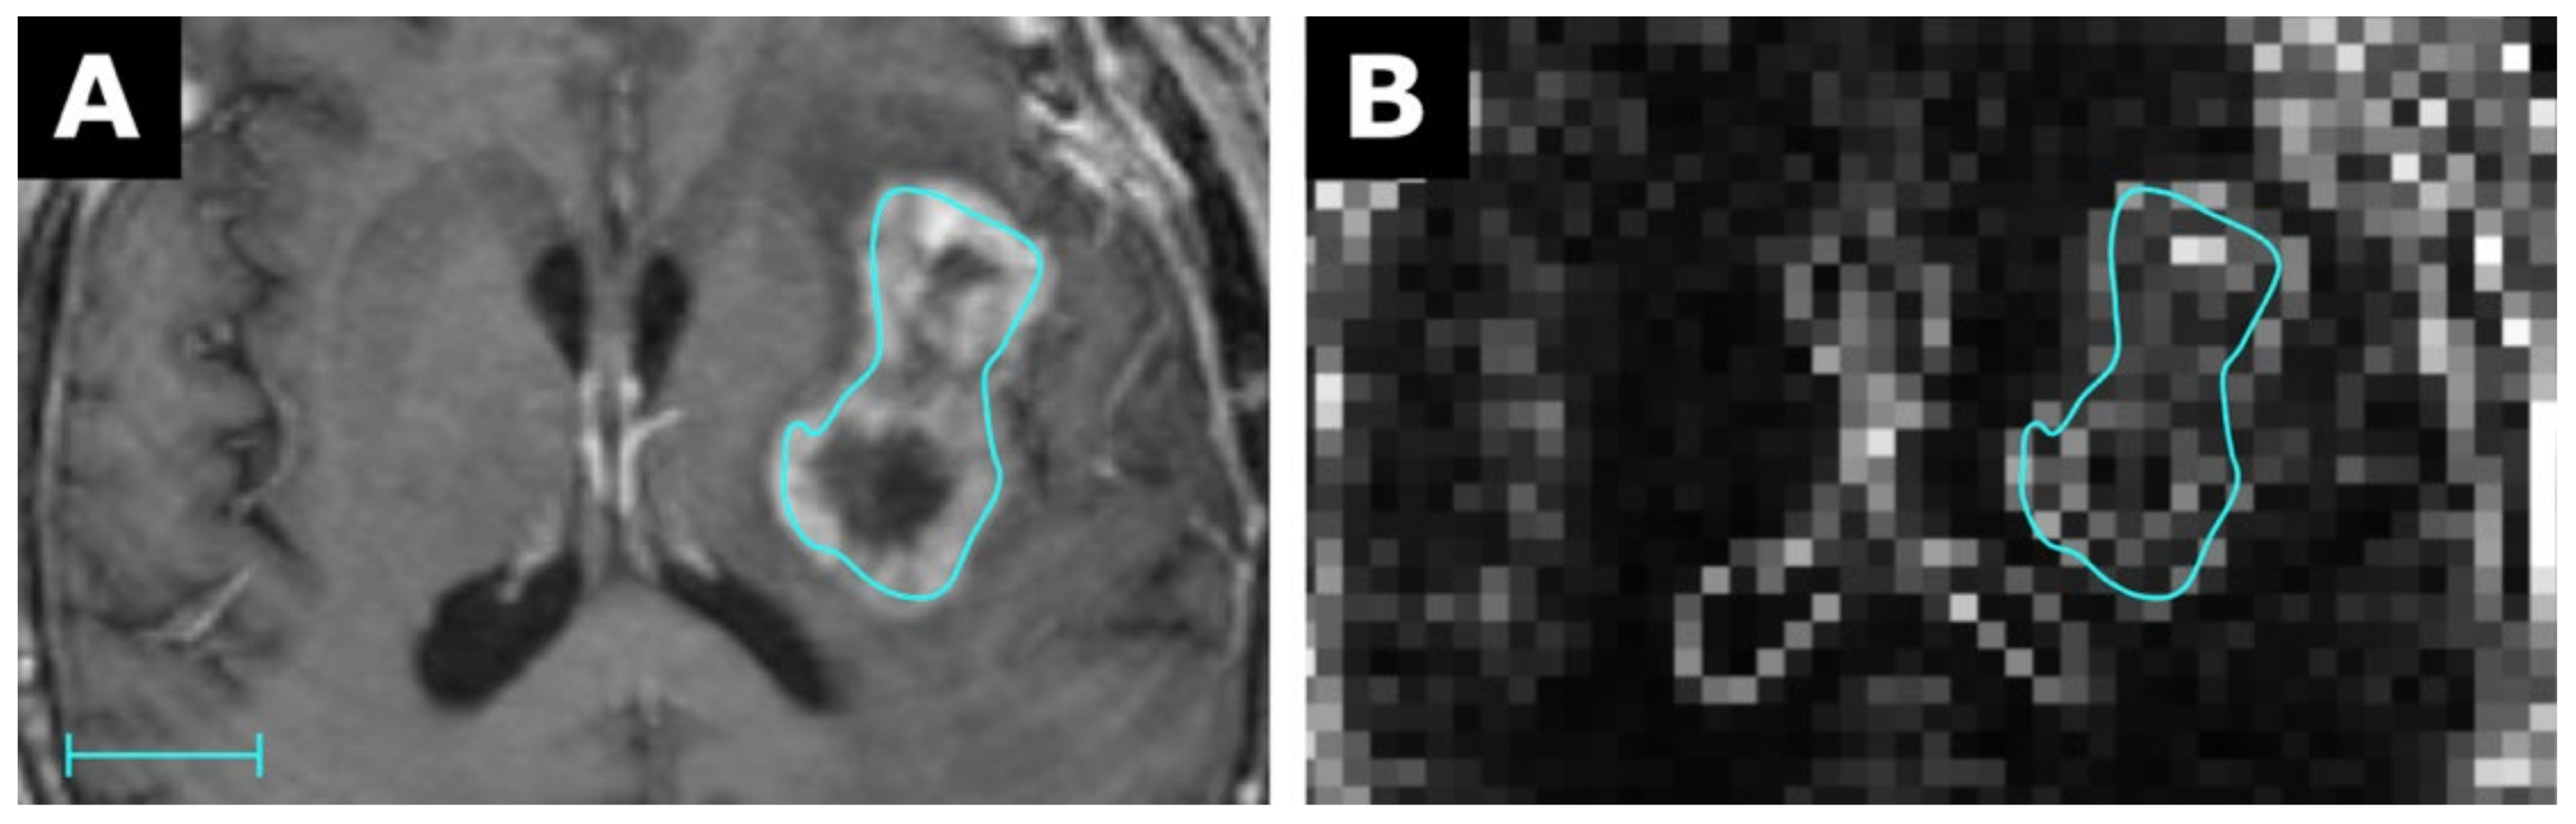

2.1. Concept of the Parametric Map Creation Tool

4.2. Parametric Map Resolution/VOI Size